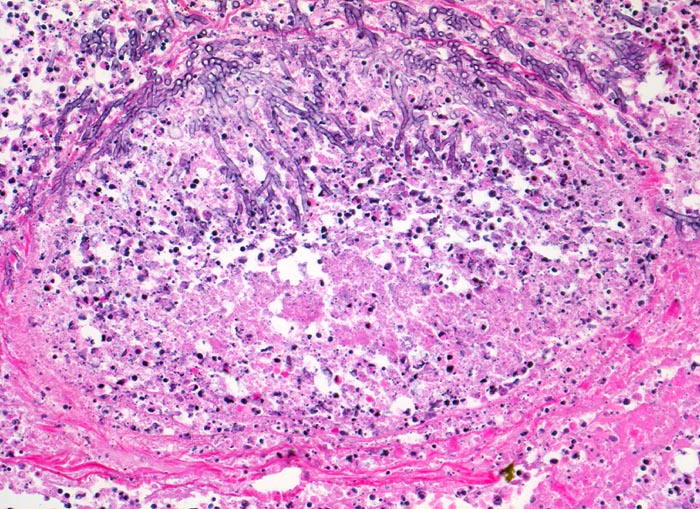

• Multiple Herde mit zentraler Nekrose und hämorrhagischem Randsaum.

• Pilzmyzelien, zerfallende neutrophile Granulozyten und Erythrozyten im Zentrum der Herde.

• Kräftig gefärbte Pilzhyphen mit 45° Verzweigungen.

• Hämorrhagischer Randsaum um die Nekrose: Hyperämische Alveolarwandkapillaren. Alveolen angefüllt mit Blut, Fibrin und Alveolarmakrophagen.